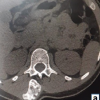

Multiple bilateral centrilobular and subpleural nodules, each <3 mm, were appreciated on high-resolution CT scan, as they are <1 cm, they are non-specific, and not considered to be metastatic in nature.

The patient also underwent a positron emission tomography (PET) scan after the surgery, which showed no evidence of metastasis. Later, the patient underwent wide excision and histopathology confirmed the diagnosis of benign osteochondroma (Figs. 7, 8, 9).